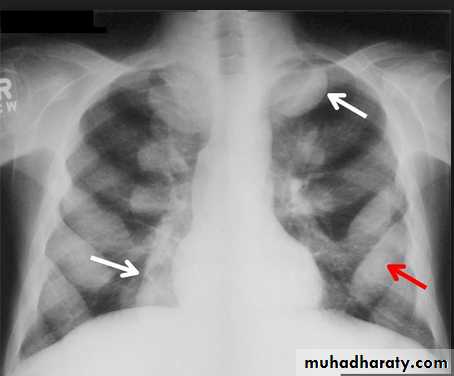

• Alveoiar oedema (‘Bat’s wings’)

• Kerlev B lines (interstitial oedema)• Prominent upper lobe vessels

• Cardiomegaiy

• Pleura

• effusionKerley A lines (Arrows), Kerley B lines (arrowheads)